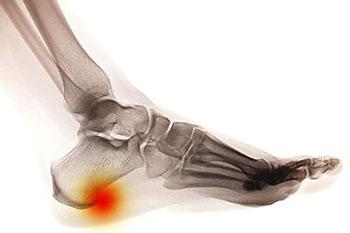

Heel spurs

A heel spurs is a foot condition created by a calcium deposit causing a bony protrusion on the underside of the heel bone. Heel spurs often start in the front of your heel and eventually affect other parts of your foot. Although heel spurs are often painless, they can cause heel pain. They often start in the front of […]